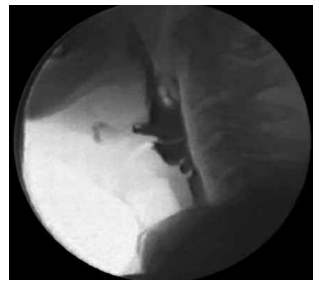

Analise a figura a seguir, que apresenta um exame de imagem realizado para avaliação da deglutição: Enunciado 4493034-1 (Geraldo P. Jotz e Elisabete C. Angelis, Disfagia: abordagem clínica e cirúrgica – criança, adulto e idoso)

Assinale a alternativa que apresenta corretamente o exame e a respectiva interpretação.